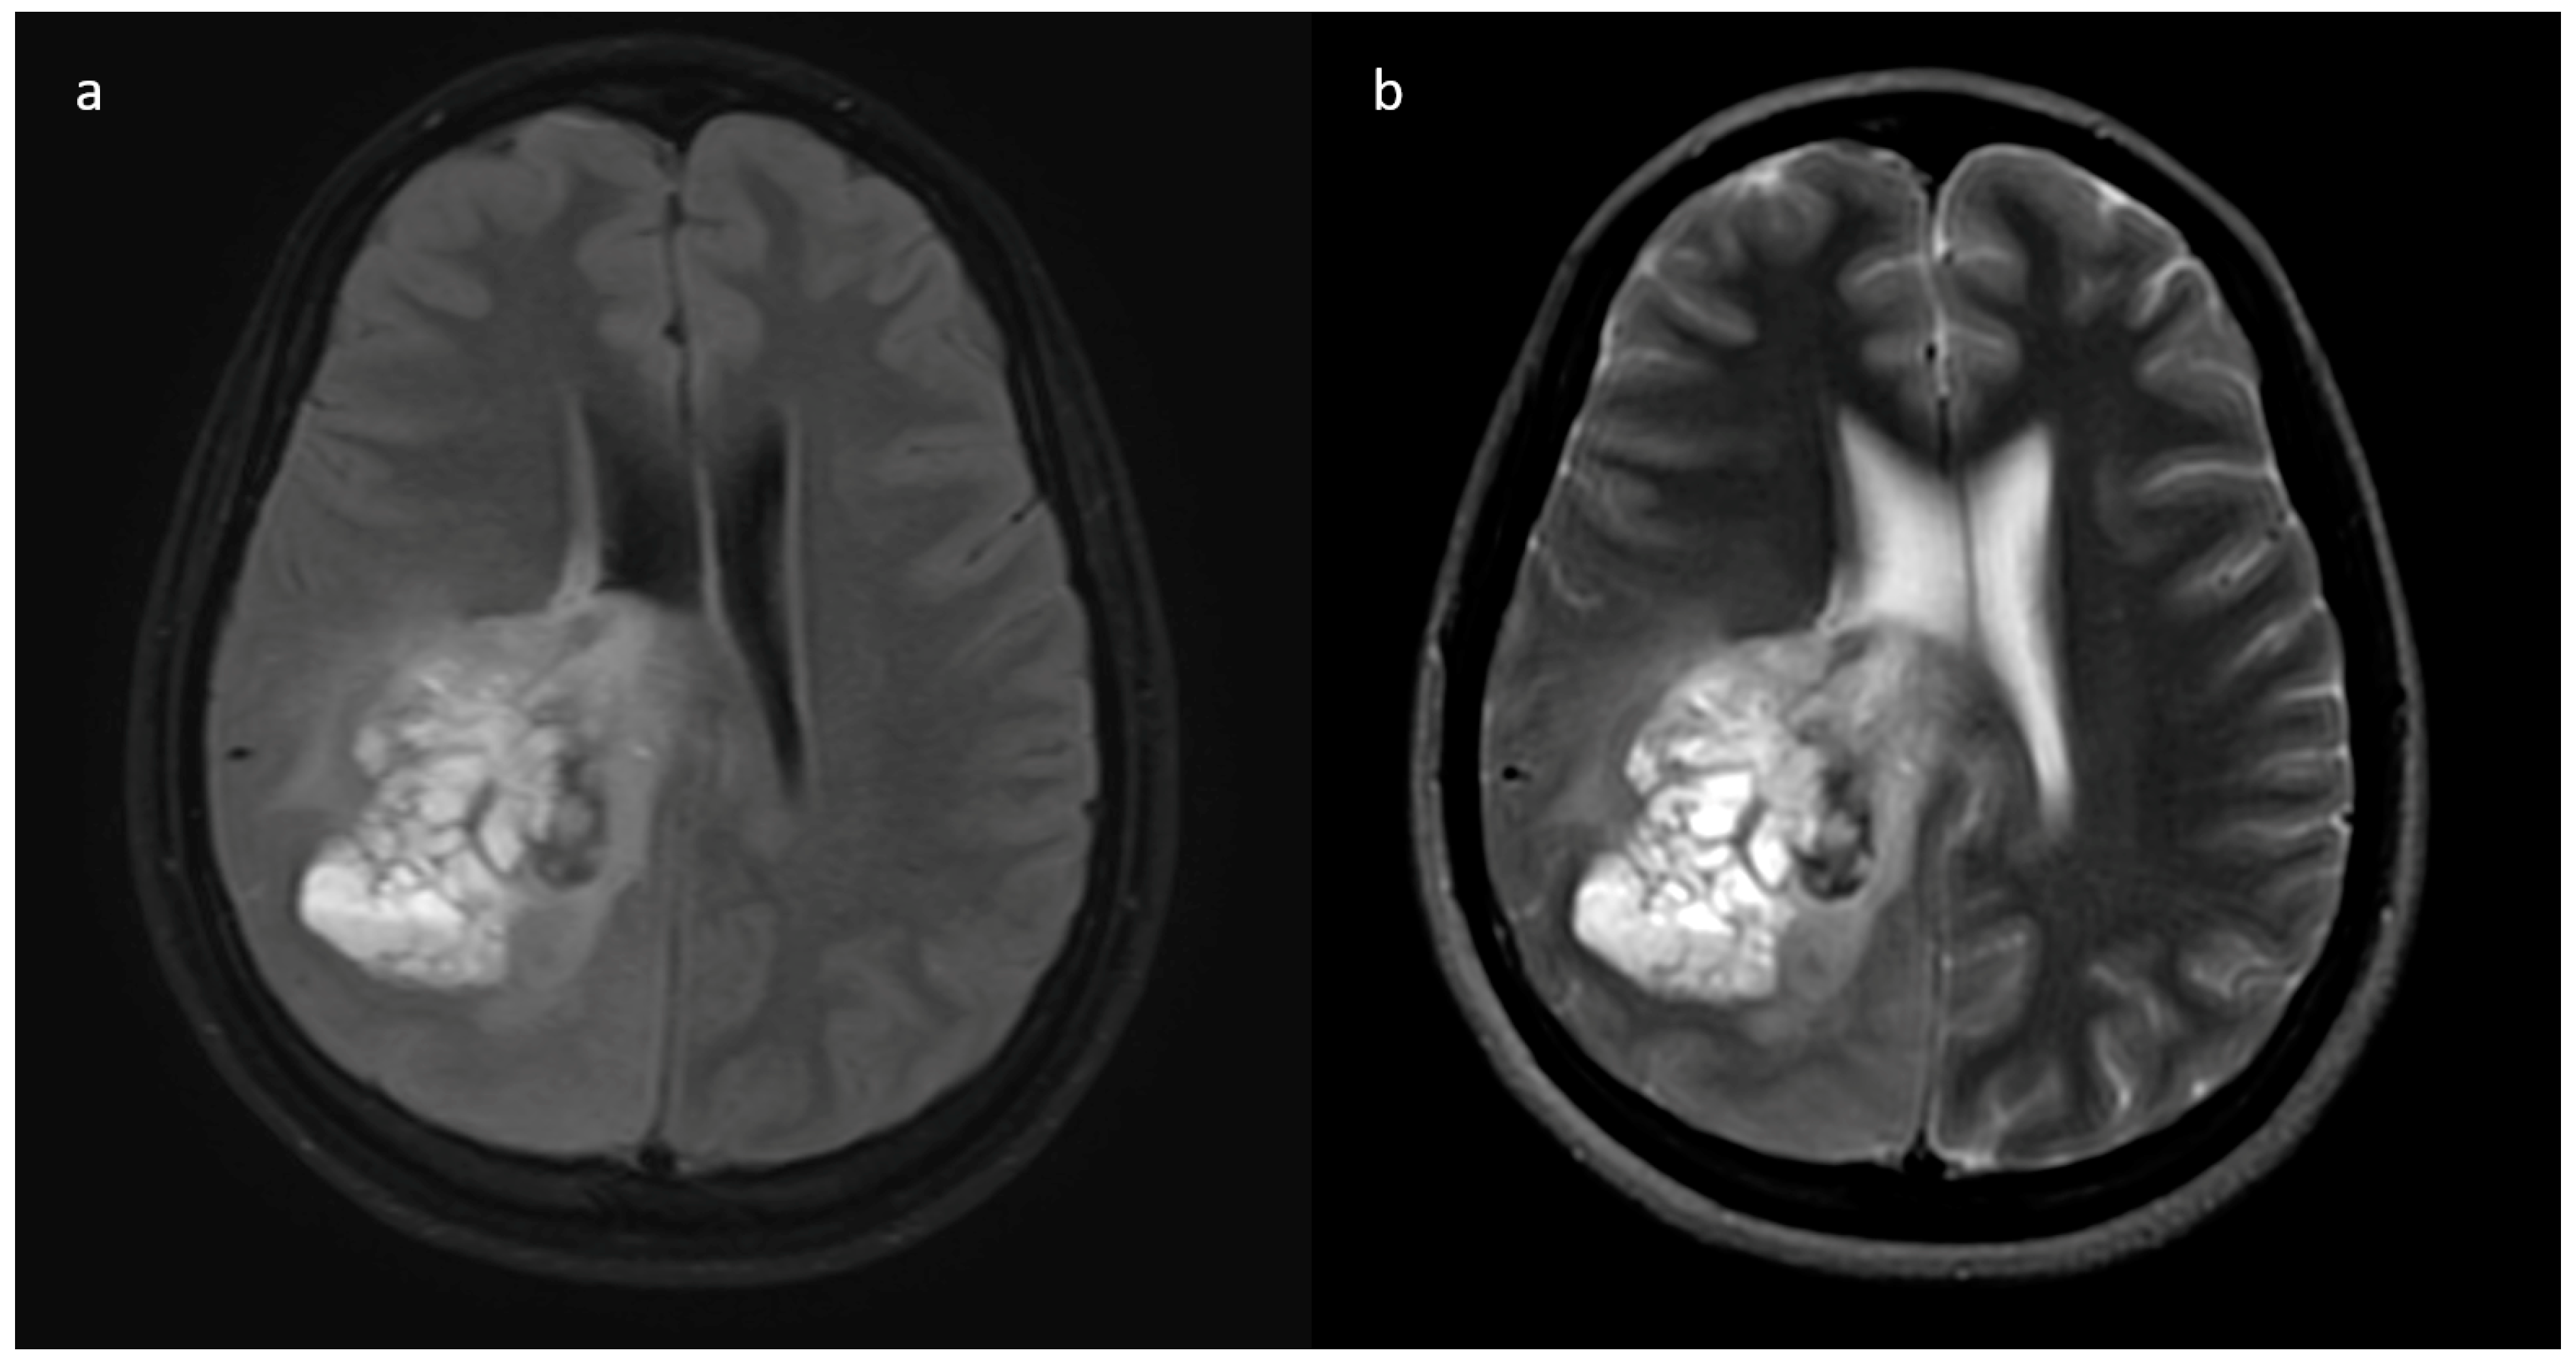

| Enhancement I | Mild | 9 (47.4) | 5 (3.9) | <0.001 |

| Moderate | 6 (31.6) | 25 (19.4) | ||

| Severe | 4 (21.1) | 99 (76.7) | ||

| Enhancement III | Rim | 6 (31.6) | 104 (80.6) | <0.001 |

| Nodular | 0 | 2 (1.6) | ||

| Patchy | 11 (57.9) | 13 (10.1) | ||

| Solid | 2 (10.5) | 10 (7.8) | ||